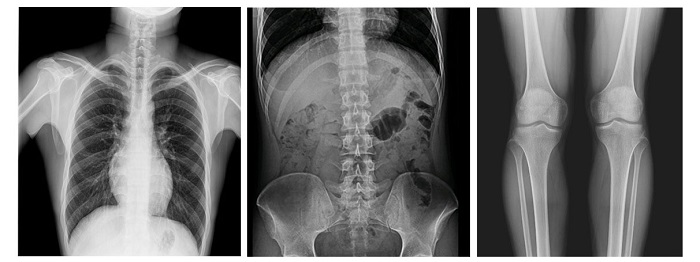

配備新一代動(dòng)態(tài)平板探測(cè)器,17×17英寸大幅面成像,能對(duì)患者的胸部腹部等部位實(shí)現(xiàn)大范圍全覆蓋,透視檢查無(wú)需對(duì)患者重新定位便可觀察到足夠大的人體器官組織,避免漏診誤診;最高30幀/s采集幀速,影像更加流暢,便于使醫(yī)生觀察細(xì)微病變,從而提高診斷準(zhǔn)確率。